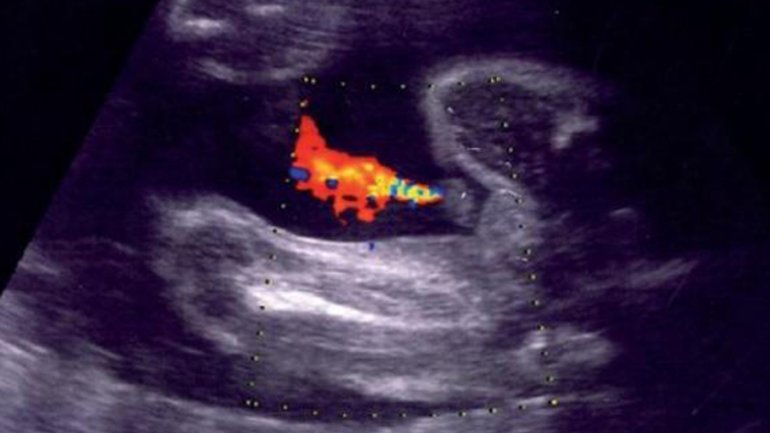

Ultraschall 16. SSW

Auf dem Ultraschallbild ist die Nabelschnur zu sehen; sie versorgt das Baby mit Nährstoffen und Sauerstoff und transportiert Abfallstoffe ab. Der Blutfluss in den drei Blutgefäßen (1 Vene, 2 Arterien) lässt sich mithilfe des sogenannten Dopplerultraschalls farbig darstellen und untersuchen.